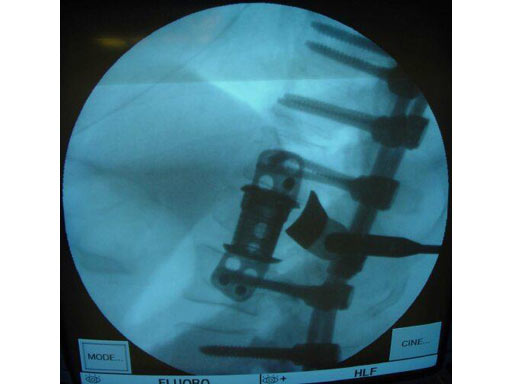

Pathology: 68 - year- old male sustained a high energy C-type shear fracture of the L1 vertebra after a fall off of a bridge. The patient had received posterior fixation three weeks before this accident, but still displayed intractable leg pain. The posterior fixation consisted of Dual - Opening USS pedicle screws at T10 -T12 and L2- L3. The preoperative x- rays and MRI showed that the patient had some slippage at the L1- L2 disc and that there were still several pieces of bone impinging on the spinal canal.

Indication: Corpectomy of the L1 vertebral body.